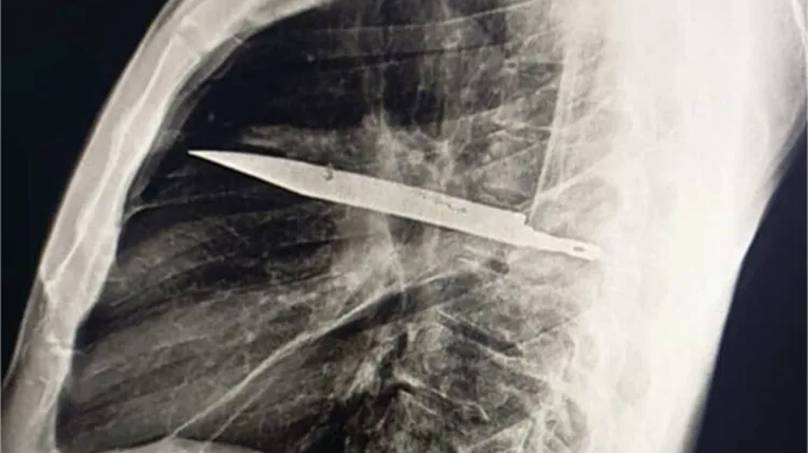

Sometimes truth is stranger than fiction, after an X-ray revealed the man had a sizeable knife buried deep inside his chest.

After ordering an X-ray, a ‘retained metallic object’ was found, and medics realised it was a knife, and it was surrounded by ‘pus and necrotic tissue’.

It had entered his body through his right shoulder.

Surgery was immediately recommended, and medics managed to retrieve the knife, and the man was deemed fit and well enough to return home just ten days later.

The man was found to have a knife embedded in his chest (National Library of Medicine)